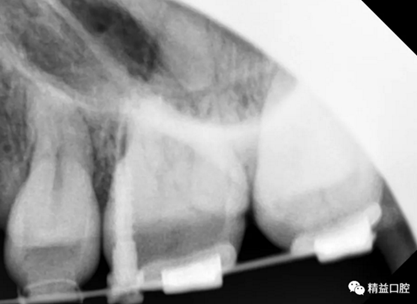

初次看到俊的牙片,我也驚訝到了,畢竟才27歲,上下門牙牙根吸收得非常嚴(yán)重,如果矯正,其中的風(fēng)險(xiǎn)還是非常大的。

從片子上可以清除看到,上牙門牙牙根吸收非常厲害。